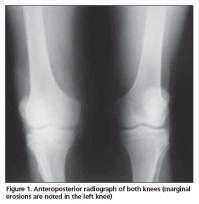

A 72-year-old male patient was admitted to our outpatient clinic with pain, swelling, and limited range of motion of the left knee, and difficulty in walking. His knee complaints had begun suddenly 1 year ago and he also had intermittent right hip joint pain. He had 1 hour of morning stiffness and his symptoms were slightly reduced by activity. He did not have any episodes of infections prior to symptom onset. He did not report fever, weight loss or sweating, and his rheumatologic history was uneventful other than his joint complaints. Despite the use of several non-steroidal anti-inflammatory drugs, there was no improvement in his knee pain, swelling, and range of motion. The anamnesis of the patient was unremarkable except he was treated for pulmonary TB 50 years ago and underwent surgery on his right hip due to trochanteric bursitis 3 years ago. On physical examination swelling and limited range of motion was observed in left knee. After activity, pain and increased temperature was also noted. His right hip joint motion was mildly painful without any limitation. Laboratory investigations revealed a white blood cell count of 6200/uL (normal range; 4800-10800/uL), hemoglobulin level of 12.8 mg/dL (normal range; 12-17 mg/dL), platelet count of 630.000/uL, erythrocyte sedimentation rate of 59 mm/h (normal range; 0-20 mm/h), blood glucose level of 110 mg/dL (normal range; 70-110 mg/dL), a C-reactive protein level of 8.99 mg/dL (normal value; <0.3 mg/dL), RF level of 63.70 IU/mL (normal value; <19 IU/mL), and anti-CCP antibody as 21.8 U/mL (normal value; 0-5 U/mL). The synovial fluid examination revealed a white blood cell count of 16.200/uL and a blood glucose level of 12 mg/dL. Marginal erosions were noted on the radiograph of the left knee (Figure 1). The anteroposterior pelvic radiograph revealed a region of ossification lateral to the right hip joint corresponding to the trochanteric bursa region. Magnetic resonance imaging (MRI) of the left knee revealed extensive hyperintense synovial thickening and erosive changes within the joint cavity, including all knee compartments and the suprapatellar bursa on T2-weighted images (Figures 2, 3). On contrast-enhanced MRI evaluation, fields of necrosis associated with infection showing peripheral enhancement were observed. Bone and joint pathologies defined in these investigations were compatible with infection. The differential diagnosis included arthritis, osteomyelitis, and especially TB, thus the Departments of Infectious Diseases, Chest Diseases, and Orthopedics were consulted. The Department of Infectious Diseases recommended that two consecutive joint aspiration samples should be screened for acid-resistant bacilli (ARB). Indeed, ARB were detected in both joint aspiration fluid samples. On lung tomography, as recommended by the Department of Chest Diseases, revealed fibrotic scars in the bilateral upper lobes, which were thought to be secondary to previous infection. Arthroscopic debridement was performed by the Department of Orthopedics and the biopsy result was compatible with a granulomatous inflammatory reaction. The patient was diagnosed with TB arthritis and treated accordingly. Clinical and laboratory improvement was noted on follow-up.